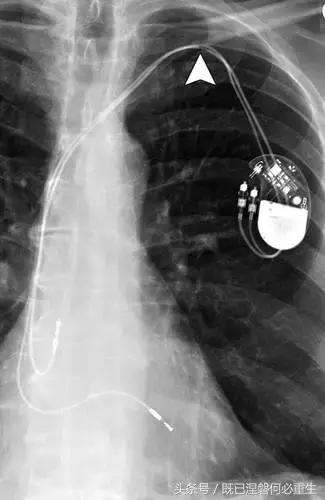

图5AB 在两个不同的患者电极错位和心室穿孔的例子。A,72岁的女性电极错误。 正位(A)和外侧(B)胸部X光片显示圣犹达医学双心室植入式心律转复除颤器与上腔静脉不适当的心房导线位置。 心房导联(箭头,A和B)的尖端高于右心房的水平,并且已经不适当地定位在上腔静脉中。 关注冠状窦引线(箭头B)的正常位置是在侧向投影中右心室(RV)引线的后方。

图5C,70岁女性心室穿孔。 正位胸片显示,圣犹达医疗双室起搏器的RV导联(箭头)超出心室轮廓。 心肌穿孔很少会导致放血或压塞。 患者没有受到并发症或随后的铅改变的不良影响(修订电极显示)。 心室穿孔可能导致对膜片的不适当刺激。